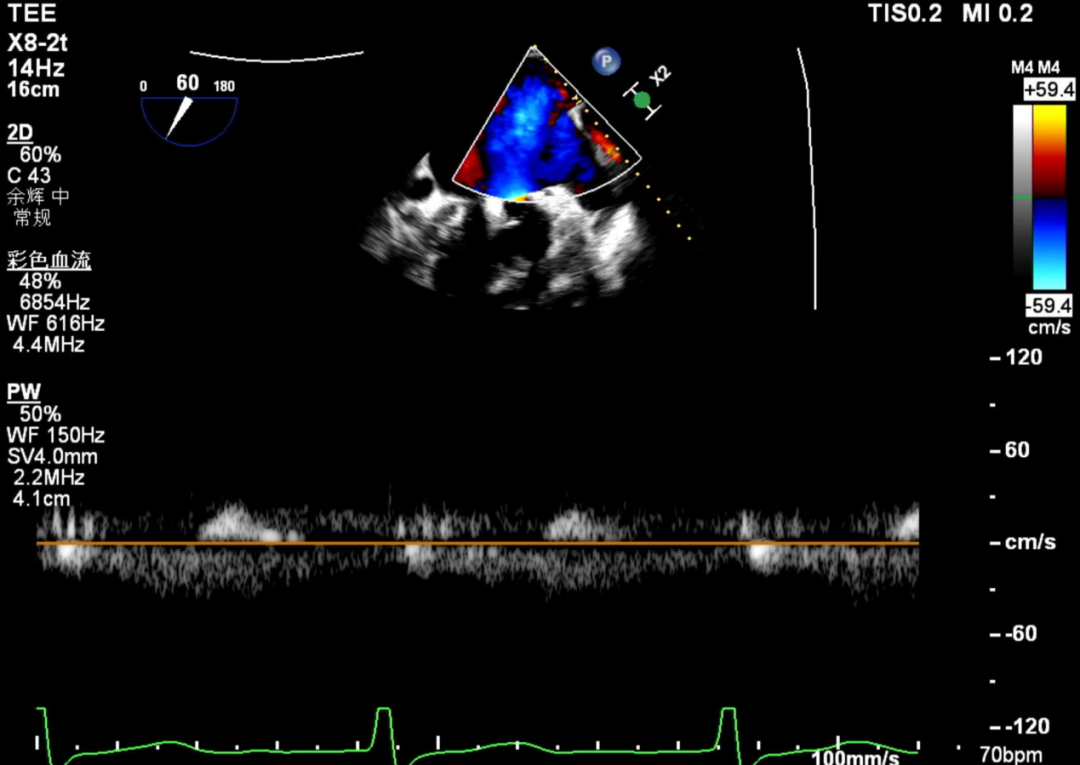

第1枚夹子释放后压差

送入第二枚SW0609(短宽型)二尖瓣夹,使其紧贴第一枚夹子。在食道心脏超声三维多平面重建(3D-MPR)引导下,将夹子跨瓣送入左心室。首次尝试捕捞并夹持瓣叶后关闭夹子,外侧反流量仍较多;随后反转夹子并重新捕捞夹持成功,此时前后叶活动均受限,外侧反流显著减少。释放夹子后,三维超声显示组织桥稳定,反流减轻至轻中度,平均跨瓣压差未见狭窄征象,肺静脉逆流亦有所改善。

第2枚夹子释放后压差

术后残留瓣口面积3.95cm²

术后肺静脉频谱